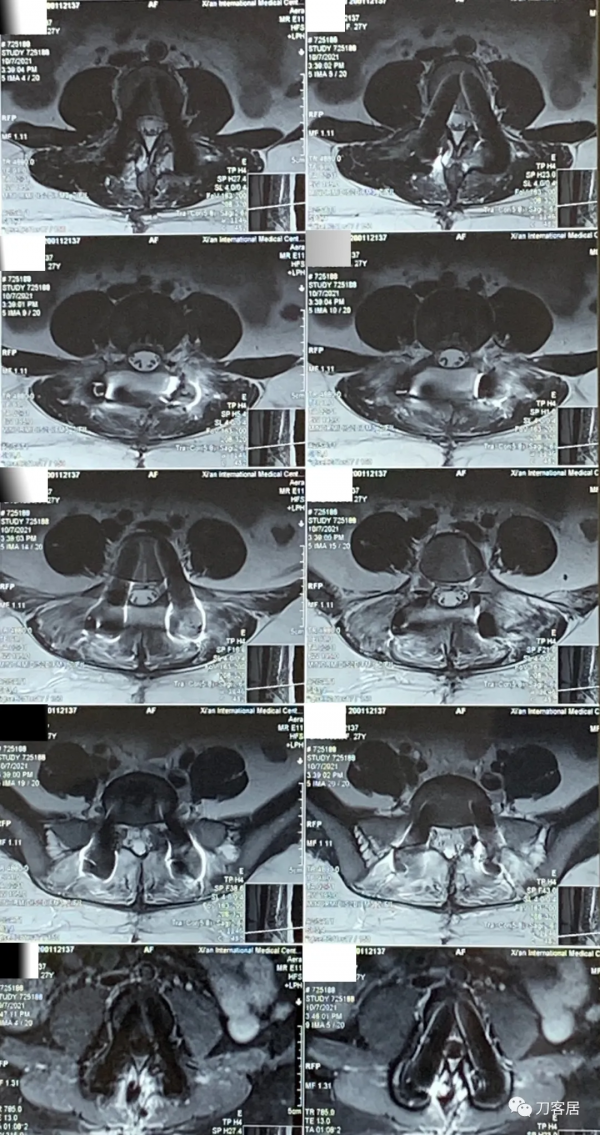

圖16. 20210904術後11天,腰椎MRI橫截面掃描,可見切口內訊號混亂,切口內液性聚集。

圖17. 20210904術後11天,腰椎MRI橫截面掃描,可見切口內訊號混亂,切口內液性聚集。

圖18. 20210920術後27天,腰椎MRI矢狀面,提示切口內訊號混亂,液性聚集。

圖19. 20210920術後27天,腰椎MRI橫截面,提示切口內訊號混亂,液性聚集。

圖20. 20211007術後44天,腰椎MRI提示腰椎切口內液性聚集,但切口周圍軟組織內混雜訊號好轉。

圖21. 20211007術後44天,腰椎MRI提示腰椎切口內液性聚集,但切口周圍軟組織內混雜訊號好轉。